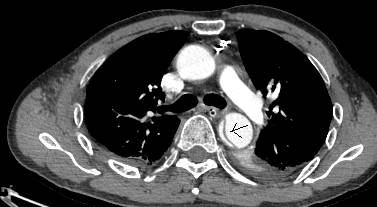

病例六

平扫CT提示降主动脉内膜片影(白箭头所示),CTA显示为B型主动脉夹层。